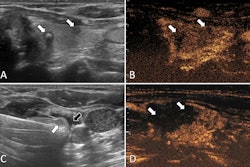

Radiology researchers continue to explore how machine-learning techniques can address current limitations in risk stratification and disease prediction. TI-RADS, which offers structured criteria for assessing thyroid nodules, is susceptible to interobserver variability, the researchers noted. This leads to inconsistent clinical decision-making.

With this in mind, Li and colleagues developed their deep learning models, which combined clinical and radiological features with deep imaging features extracted from ultrasound scans using EfficientNet-B0. The latter is a convolutional neural network (CNN) that is trained on more than one million images from the ImageNet database.

The study included 580 patients with thyroid nodules categorized from TI-RADS 2 to 5. The researchers reported that the clinical models achieved strong predictive ability.